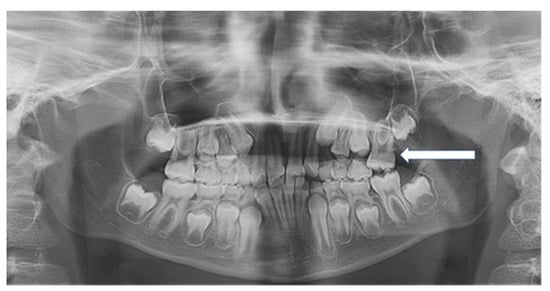

Figure 1. Panoramic radiograph showing unilateral ectopic eruption of the left permanent maxillary first molars (arrow) in a 7-year-old patient.